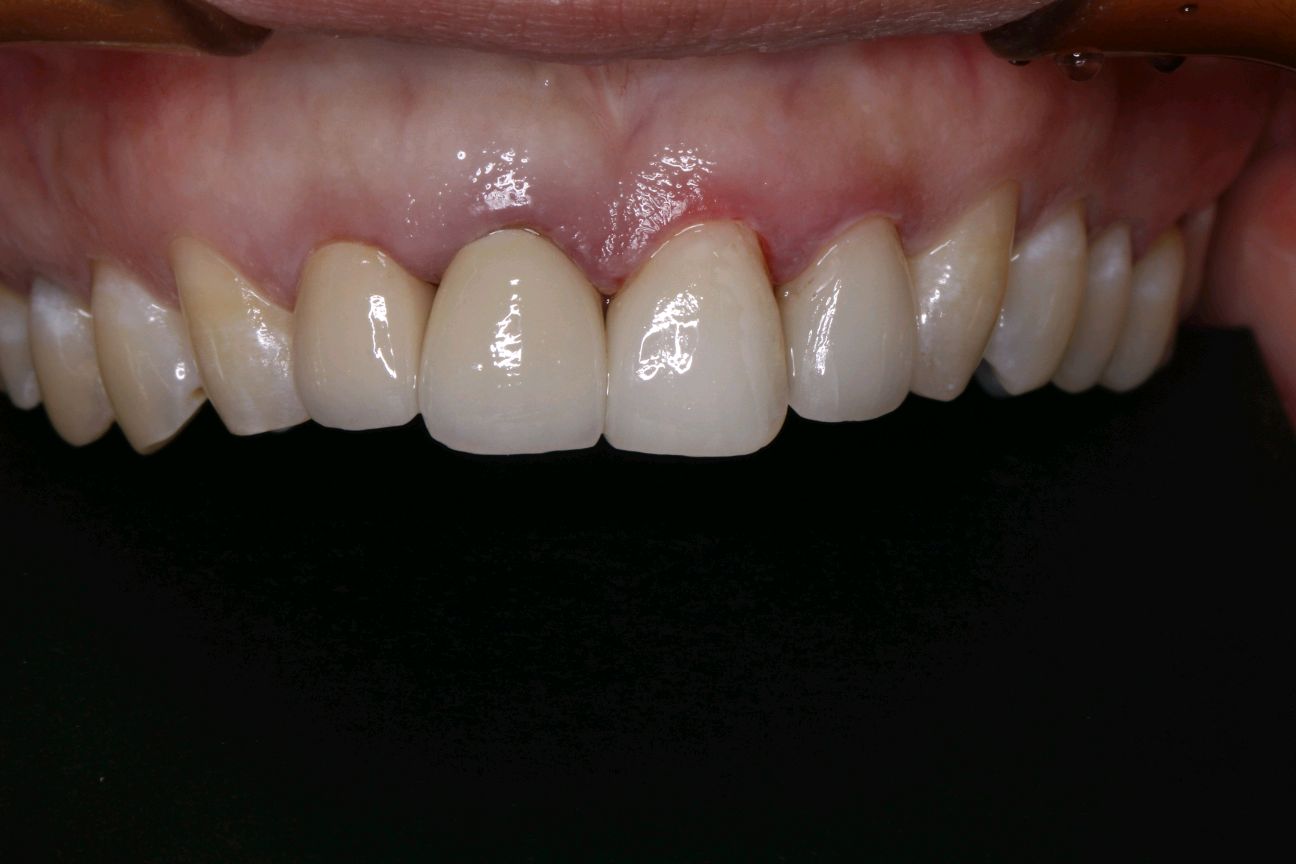

术中